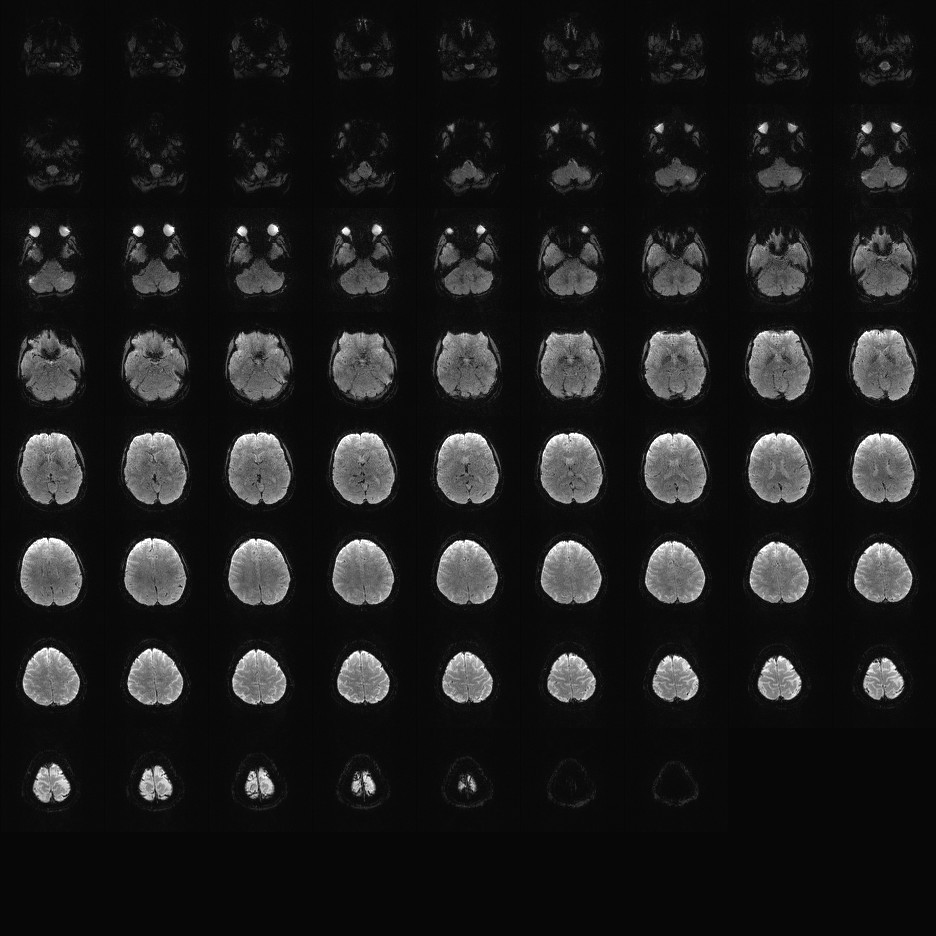

Multi-banded RF pulses can be used to accelerate volume coverage along the slice direction by simultaneously exciting and acquiring multiple slices and subsequently unaliasing them using parallel imaging principles and the spatial information available in multi-channel RF array coils.

This allows for a direct reduction in the volume TR by the number of simultaneously excited slices (i.e., the multiband (MB) factor or the slice acceleration factor).